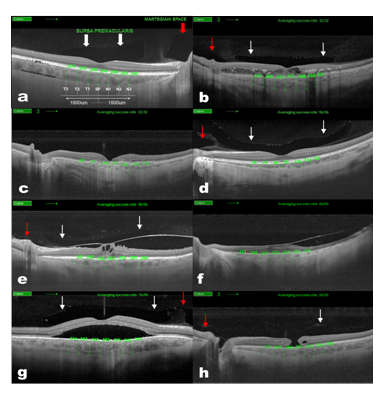

All scans were performed using the Topcon® SS-DRI-OCT. This system operates at a speed of 100,000 A-scans/second using a wavelength of 1,050nm produced by a wavelength tunable laser as a light source. The claimed axial resolution is 8 μm, the lateral resolution is 20 μm and the imaging depth in tissue is 2.3mm. Scans are averaged to reduce noise. The system is equipped with a tracking system to improve reproducibility. The 12mm long 5 raster lines cross pattern (5 lines vertical and 5 lines horizontal) default setting was used in a vitreous focal mode and centred on the fovea (Figure 1) to identify the presence or absence of a BPM, SM and measure the CT in each eye. The space among the top and the bottom line of the 5LineCross pattern was set at 1.5 mm.

Figure 1 Choroidal thickness measurement in normal (A) Diabetic Retinopathy, (B) AMD, (C) myopic, (D) VMA and/or VTM, (E) RP, (F) CSR, (G) and miscellaneous, (H) patients. Swept-Source Deep Range Imaging Optical Coherence Tomography (SS-OCT) 5-lineCross raster scan demonstrating measurement technique used to obtain choroidal thickness across the macula. This OCT also demonstrates the presence of Bursa Premacularis (white arrows) and Martegiani space (red arrows).

Contrast and brightness of the images were digitally enhanced after collection to aid the delineation of anatomic features of the cortical vitreous. Macular CT was manually determined by measuring the distance between the RPE and the choroid/sclera junction by two independent observers, using the caliper system provided by the software. The images used for the measurements were the one with less retinal thickness crossing the centre of the fovea, to measure equivalent meridians in each patient. Seven measurements were taken: one subfoveal, three further determinations every 500µm temporal up to 1500µm (T1, T2, T3) and nasal (N1, N2, N3) to fovea (Figure 1) of 54 HE and 150 MD.

The macular area of 150 MD eyes (classified in 8 sub-groups) was studied with an SS-OCT system and compared with 54 HE group. SS-OCT allowed visualization of CT in all (100%) sub-groups and also in the HE group (Figure 1). Mean age in HE group was 47±23 years (9-100) versus 57±22 years (6-92) in MD group (p<0.05 Student’s t-test) (Table 1).